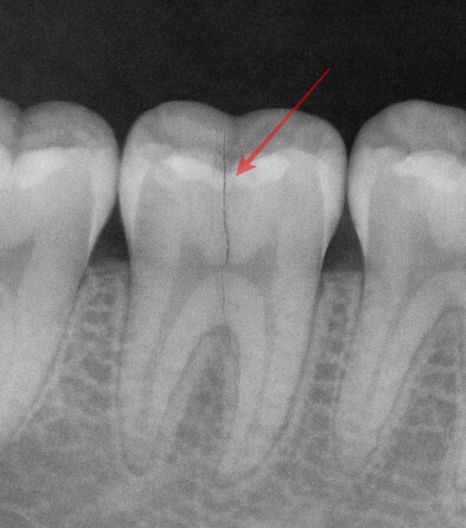

CTS가 까다로운 이유는

일반 X-ray로는 균열선이

거의 포착되지 않는다는 점에 있습니다.

이해를 돕기 위한 치아 균열 예시입니다.

균열의 방향이 방사선이

투과하는 방향과 평행할 경우

영상에 나타나지 않기 때문입니다.